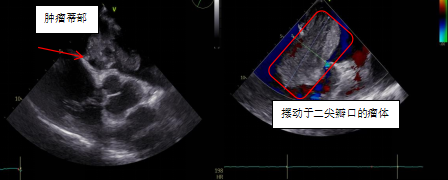

患者郑大爷,因“反复劳累性心累、气促2+月,加重10+天”到我院胸心血管外科就诊。本次病情发作后,郑大爷夜间无法平卧,呈端坐呼吸,伴咳嗽、咳痰,为白色泡沫痰,心悸、心慌明显,并感头晕,测血压偏低,为休克状态(80-90/40-50mmHg)。入院经心脏彩超、胸部影像学等相关检查,发现导致郑大爷症状的元凶:“巨大左心房占位”,支持粘液瘤样改变,同期发现患者伴有卵圆孔未闭、三尖瓣中度关闭不全等心脏问题。

术中,手术医师、体外循环师、麻醉师等医务人员精密协作,为郑大爷完整切除大小约为9cm×7cm×3cm的肿瘤,并同期关闭卵圆孔及行三尖瓣Devega成形术。术后病理明确诊断为左心房粘液瘤,经过精心治疗,郑大爷恢复顺利,心衰症状明显改善,并且在各项指标复查正常后,康复出院。

程永波副主任医师介绍到,心房粘液瘤是最常见的原发性心脏肿瘤,心脏各个房室均可发生粘液瘤,位于左心房者最多见。体积很小的粘液瘤可以没有症状,肿瘤长大后导致血流动力学改变,即可出现全身表现和周围血管栓塞等症状。左心房粘液瘤最常见的临床症状是由于房室瓣血流受阻引起心悸、气急等。移动度较大的粘液瘤若突然阻塞房室瓣瓣孔,病人可发作晕厥、抽搐,甚至猝死。粘液瘤病例明确诊断后应尽早施行手术摘除肿瘤,恢复心脏房室正常通道,避免肿瘤发生恶变以及突然堵塞房室瓣瓣口引致猝死,或者因肿瘤碎屑脱落并发全身各部位的栓塞。